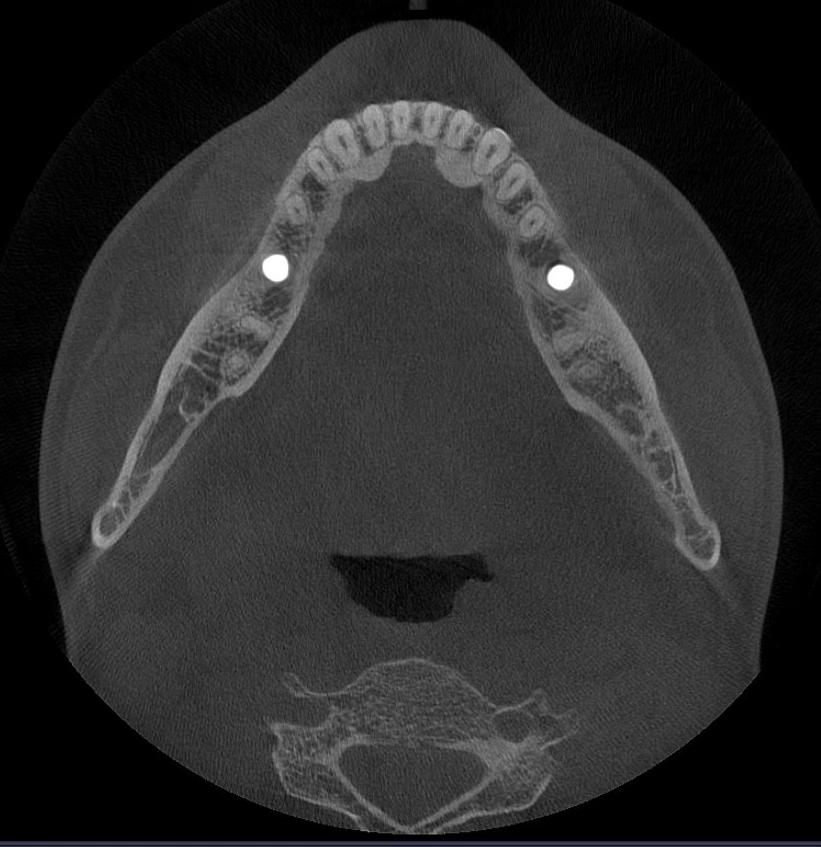

Los algoritmos matemáticos que reflejan las propiedades físicas y el avanzado motor de IA aprendido a partir de varios datos trabajan juntos para reducir el ruido y hacer que las estructuras dentales sean más claras.

Borra los artefactos metálicos y restaura con precisión las estructuras dentales, las coronas metálicas y los implantes basados en principios matemáticos.